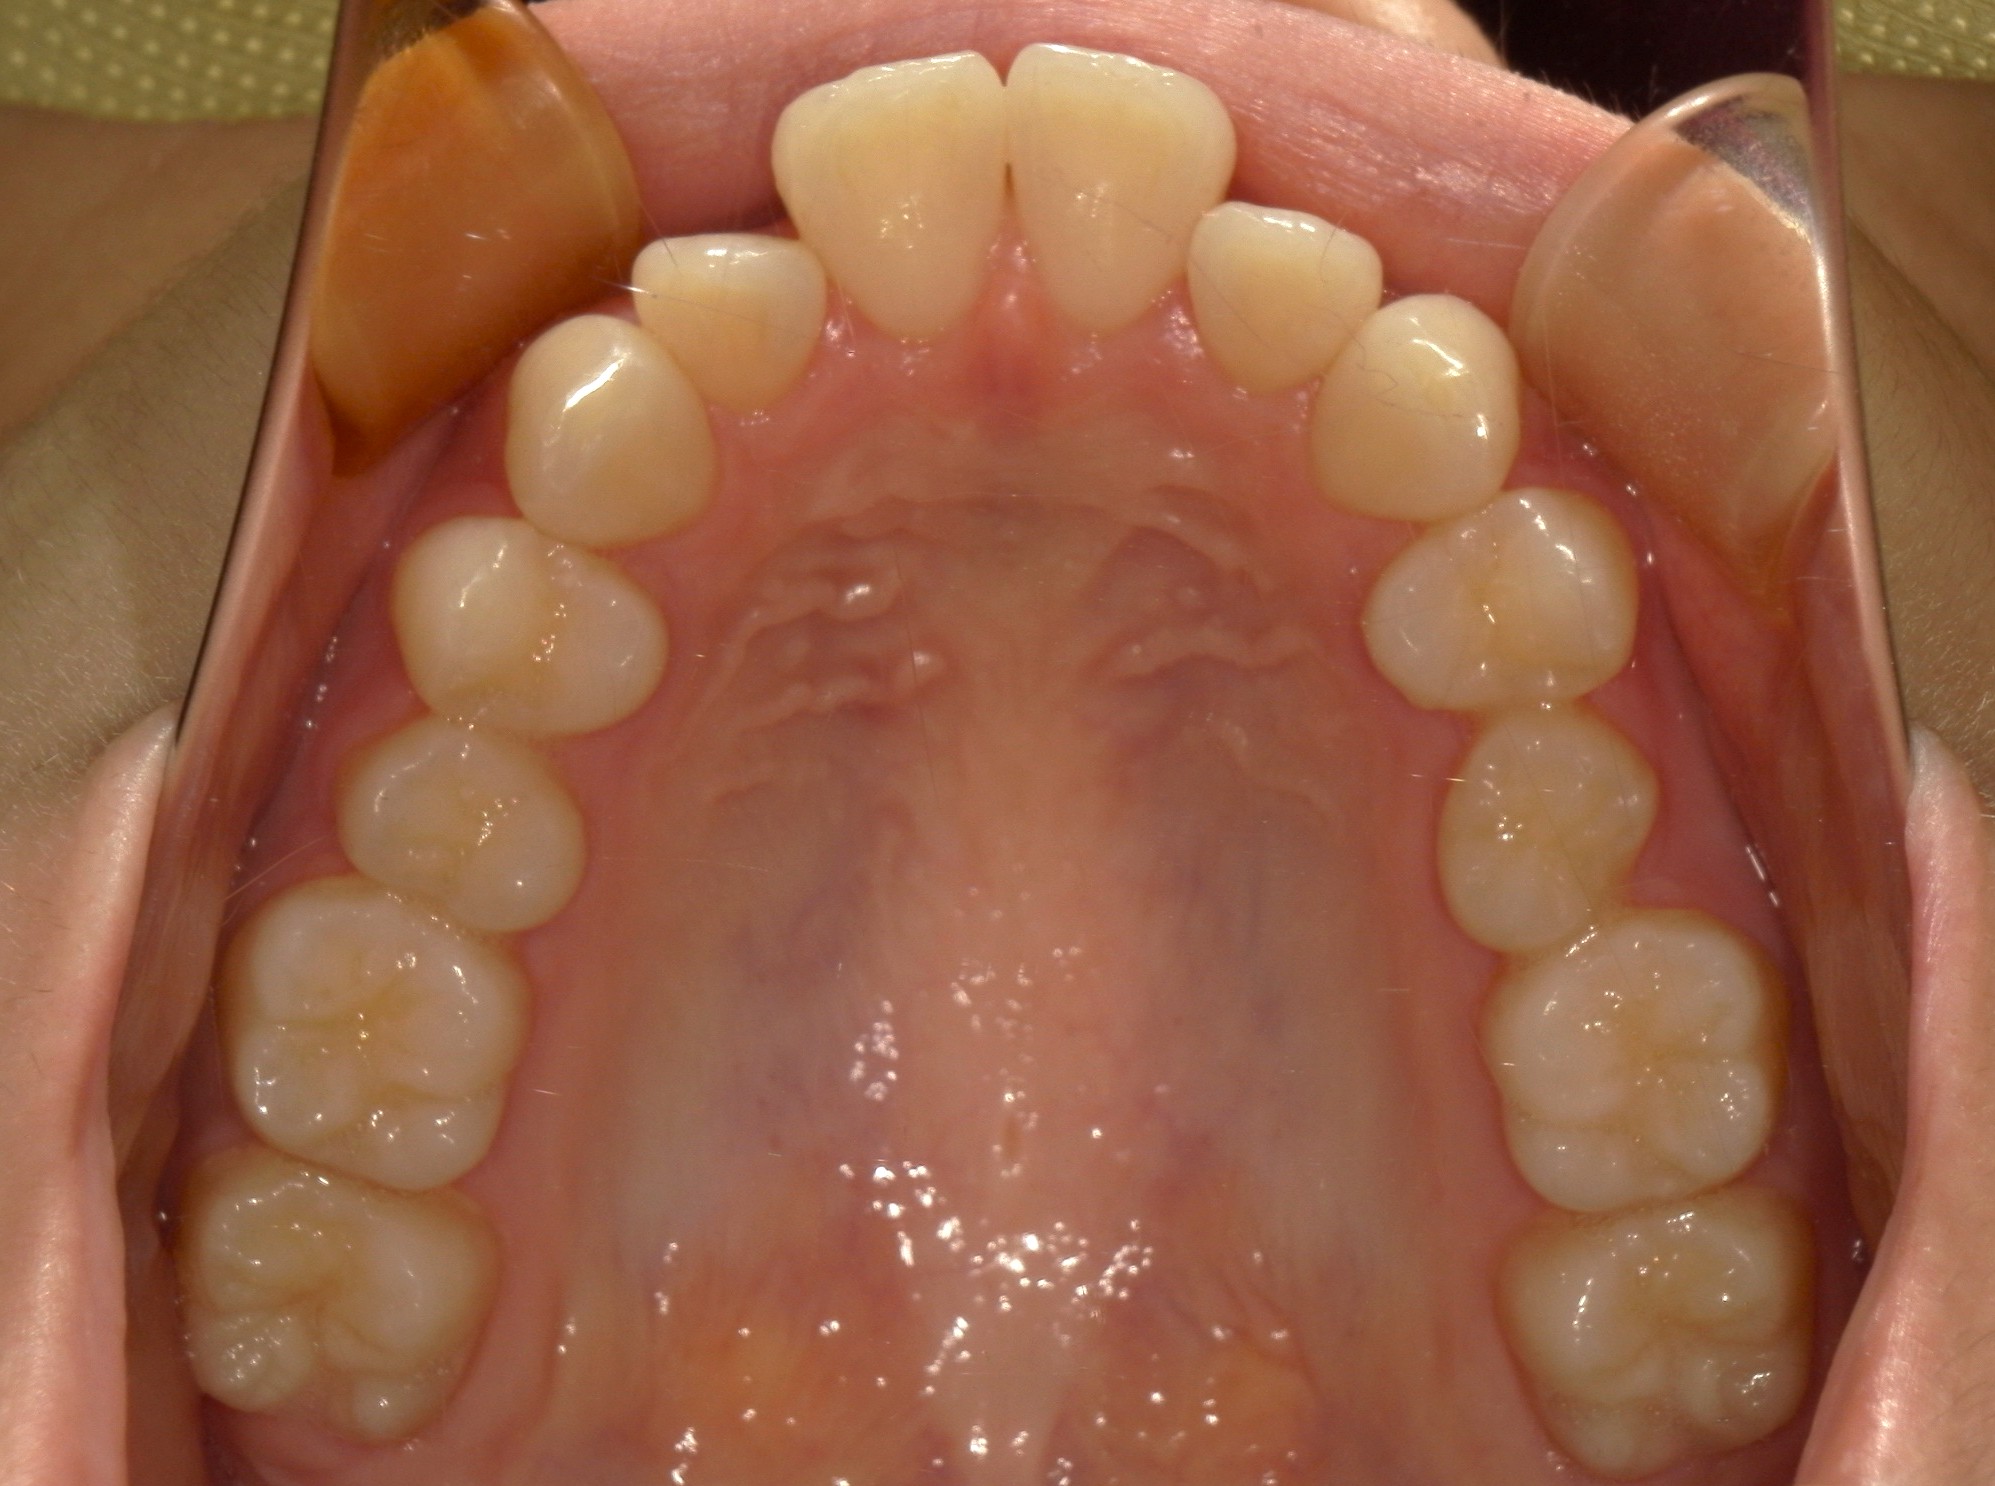

横から見た口腔内写真でよくわかるように、前歯が出っ歯になっており、全く咬んでいない状態でした。また下の前歯が本来4本あるところが、先天的に一本少なく3本しかない(Three incisors)であったため下顎のアーチが小さいというお口の状態でした。前歯を正しい傾きに治し、咬合させるため、上の歯のみ2本の抜歯を行うこととしました。下の前歯が3本のため、その正中に注意しながら前歯の傾きを修正し、奥歯のポジションを整えて仕上げました。口元の突出感は大きく改善し、咬合も良好な状態で完了することができました。

口内上

治療前

治療後